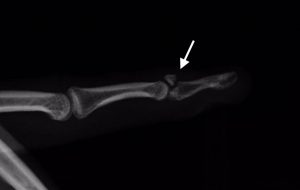

El dedo en martillo se diagnostica fundamentalmente mediante la exploración física del Cirujano de Mano.  Las radiografías simples son útiles para determinar la presencia de una fractura-avulsión (Figura 4).

Figura 4 - Radiografía de Fractura-avulsión del tendón extensor terminal (bony-mallet)